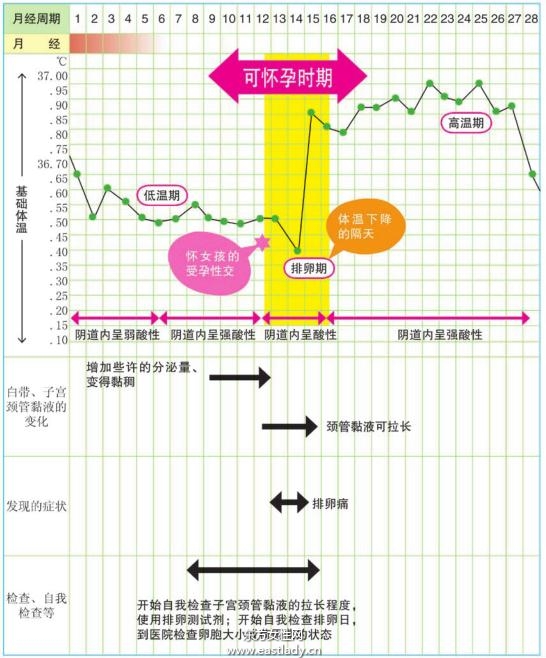

- 如何测排卵期 排卵期的症状有哪些

如何测排卵期 排卵期的症状有哪些,随着社会和医学的发展,很多人的思想也发生了翻天覆地的变化。比如原本随便的要孩子,变成了现在有准备的要孩子。现今社会,更多的人都愿意重视备孕,将生一个优质宝宝的因素提早到了备孕期间。还有的也比较注重女性的排卵期,想知道如何测排卵期。其实女性排卵期的表现和症状还是很明显的,很多人在家就可以自测排卵期。今天小编为大家带来了如果测排卵期的方法和排卵期的症状,大家要认真学习哦。...

- 排卵期体温有什么变化 如何从体温变化看排卵期

排卵期体温有什么变化 如何从体温变化看排卵期,想要备孕的或者避免意外怀孕的女性朋友们,都非常的注重自己的排卵期,因为在排卵期进行性交的话会更容易怀孕,所以大多数女性朋友们都会掌握自己的排卵期,其实排卵期也是有规律可循的,而本文要为大家介绍的就是教大家学会如何看排卵期体温来辨别是非为排卵期。...